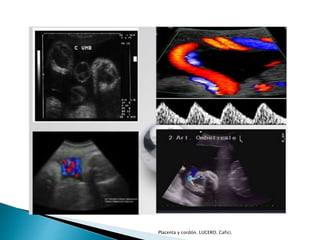

Cordón umbilical

Placenta y cordón. LUCERO. Cafici.

 Visualizado

◦ 8s

◦ Longitud

 Similar a LEM

 Dos arterias

 Una vena

 Gelatina de Wharton

◦ Une y contiene a los vasos del cordón, los protege.

◦ Compuesta de fibras de colágeno que forman una red de

cavidades interconectadas, espacios cavernosos y

perivasculares.

◦ Alteraciones

 DM, HTA, RCIU

 Tamaño

◦ Diámetro <2 cms

◦ Disminución del diámetro

 Preeclampsia

 Muerte fetal

 Pequeño para edad gestacional

◦ Aumento del diámetro

 Diabetes gestacional